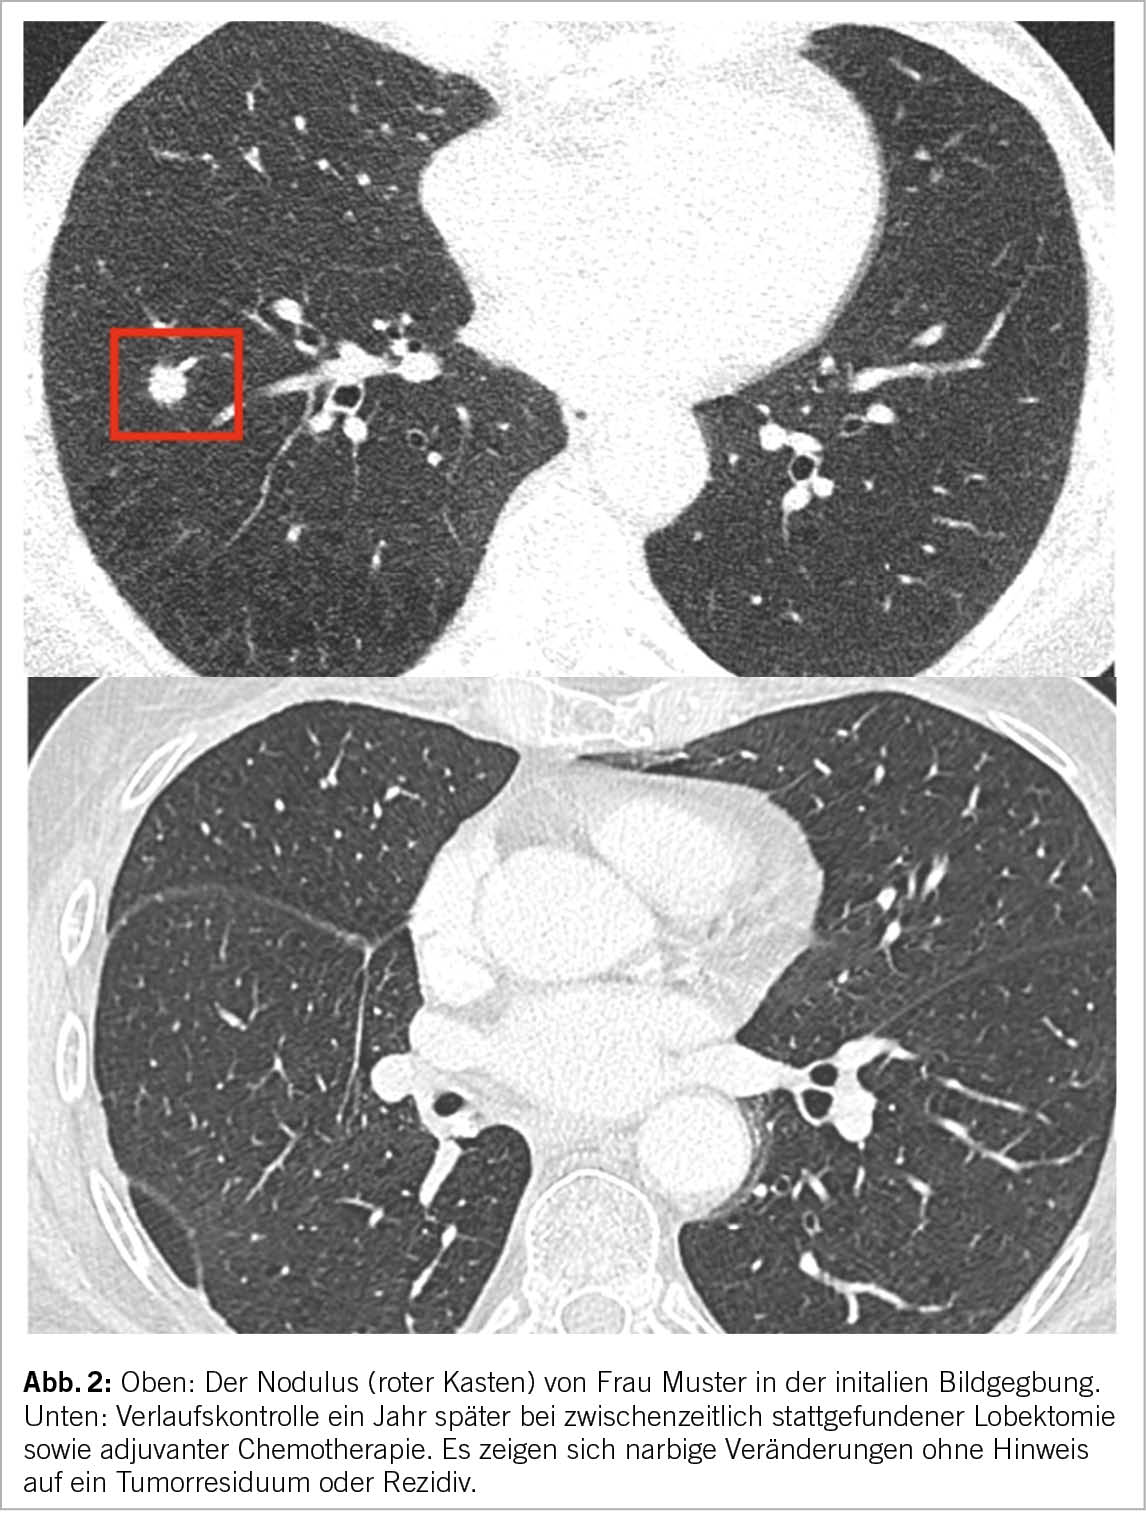

Jede neue Früherkennungsmassnahme muss vor der Übernahme durch die obligatorische Krankenpflegeversicherung auf ihre Wirksamkeit, Zweckmässigkeit und Kosteneffizienz geprüft werden. Diese Beurteilung wird von der Eidgenössischen Kommission für allgemeine Leistungen und Grundsatzfragen (ELGK) vorgenommen, nachdem die betroffenen Kreise beim BAG ein Gesuch eingereicht haben. Als Grundlage hierfür müssen konkrete handlungsleitende Empfehlungen vorliegen. Dieser Herausforderung stellen sich die involvierten Fachgesellschaften zusammen mit den Patientenorganisationen Lungenliga Schweiz und Krebsliga Schweiz. Ein HTA (Health Technology Assessment), welches Abläufe und Empfehlungen zum Screening beinhaltet, wurde im vergangenen Mai von der Kommission für Krebsfrüherkennung veröffentlicht und anschliessend mit verschiedenen Stakeholdern besprochen. Am 15. November 2022 veröffentlichte die Kommission eine offizielle Empfehlung zum Screening mittels niedrigdosierter Computertomographie für Risikogruppen (17). Die medizinische Indikation für ein Niedrigdosis-CT-Screening müsste in jedem Fall von einem Arzt gestellt werden, um von der obligatorischen Krankenpflegeversicherung übernommen zu werden. Vorläufige Studienergebnisse einer Schweizer Pilotstudie, in welche Patienten mit erhöhtem Risiko (in Anlehnung an die NELSON Kriterien oder mit einem PLCOm2012 >2.5%) eingeschlossen wurden, zeigt vielversprechende Ergebnisse. Abgesehen von einem grossen Interesse der Allgemeinbevölkerung wurden nahezu 5% der Teilnehmer mit Lungenkrebs diagnostiziert. Jedes der detektierten Lungenkarzinome konnte mit Hilfe eines kurativen Ansatzes behandelt werden (Abb. 2).